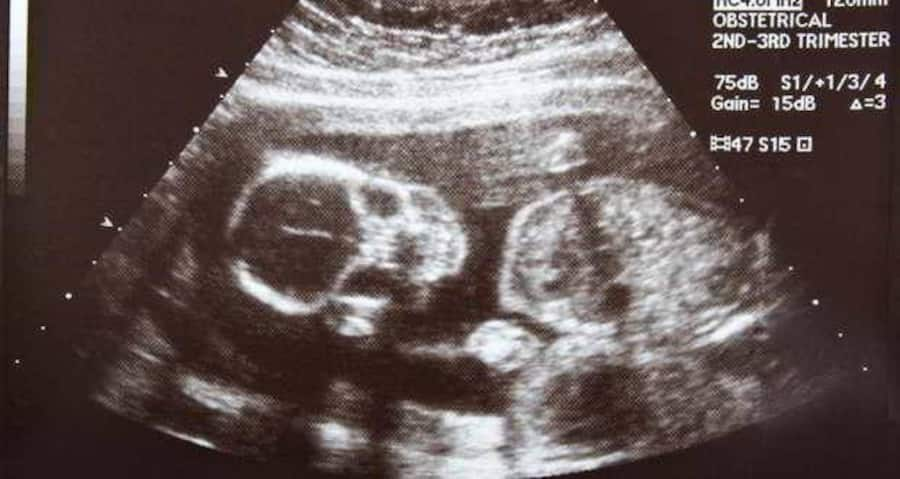

Foetus-211A hand-held scanner, costing as low as 40 pounds and of the size of a computer mouse, if plugged into any computer can reveal vital information about the foetus, that can save lives of thousands of women and children, has been developed by British engineers. The device, developed in Newcastle University could be a big help to medical teams working in the world's poorest nations with basic, antenatal information that could save thousands of lives. The device, as big as a computer mouse, works in a similar way to existing ultrasound scanners, using pulses of high frequency sound to build up a picture of the unborn child on the computer screen, according to a Newcastle statement.

However, unlike the technology used in most hospitals across Britain costing anywhere from 20,000-100,000 pounds, the scanner created by Jeff Neasham and research associate Dave Graham at Newcastle can be manufactured for as little as 30-40 pounds. Tested by experts in the Regional Medical Physics Department at the Freeman Hospital, part of the Newcastle upon Tyne Hospitals NHS Foundation Trust, the scanner produces an output power that is 10-100 times lower than conventional hospital ultrasounds.